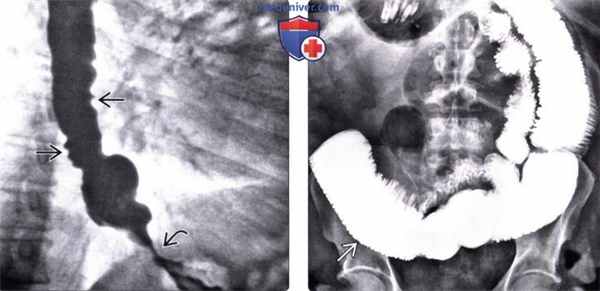

(Слева) На рентгенограмме пищевода, выполненной во время рентгеноскопии у мужчины 50 лет определяется отсутствие первичной перистальтики и глубокие, периодические третичные сокращения стенки пищевода. Просвет пищевода слегка расширен, видна стриктура в области пищеводно-желудочного перехода.

(Справа) На рентгенограмме, выполненной спустя два часа после рентгеноскопии этому же пациенту, определяется выраженное замедление прохождения контраста по тонкой кишке. Складки тощей кишки истончены и близко прилежат друг к другу, просвет кишки расширен, перистальтика выражена минимально: эти изменения являются классическими признаками «истощения» кишки.

(Слева) При рентгеноскопии с контрастом у женщины среднего возраста, страдающей склеродермией, определяется дилятация и атония пищевода с наличием тугой стриктуры в области пищеводно-желудочного перехода. Пищевод медленно освобождается от бариевой взвеси, даже в положении пациентки стоя: длительное время сохраняется уровень между взвесью сульфата бария и жидкостью.

(Справа) На рентгенограмме, полученной через некоторое время у той же пациентки, определяется выраженное расширение просвета второй части двенадцатиперстной кишки с резким переходом в сужение на уровне позвоночного столба. Двенадцатиперстная кишка является вторым наиболее часто поражающимся органом ЖКТ при склеродермии; на первом месте находится пищевод.